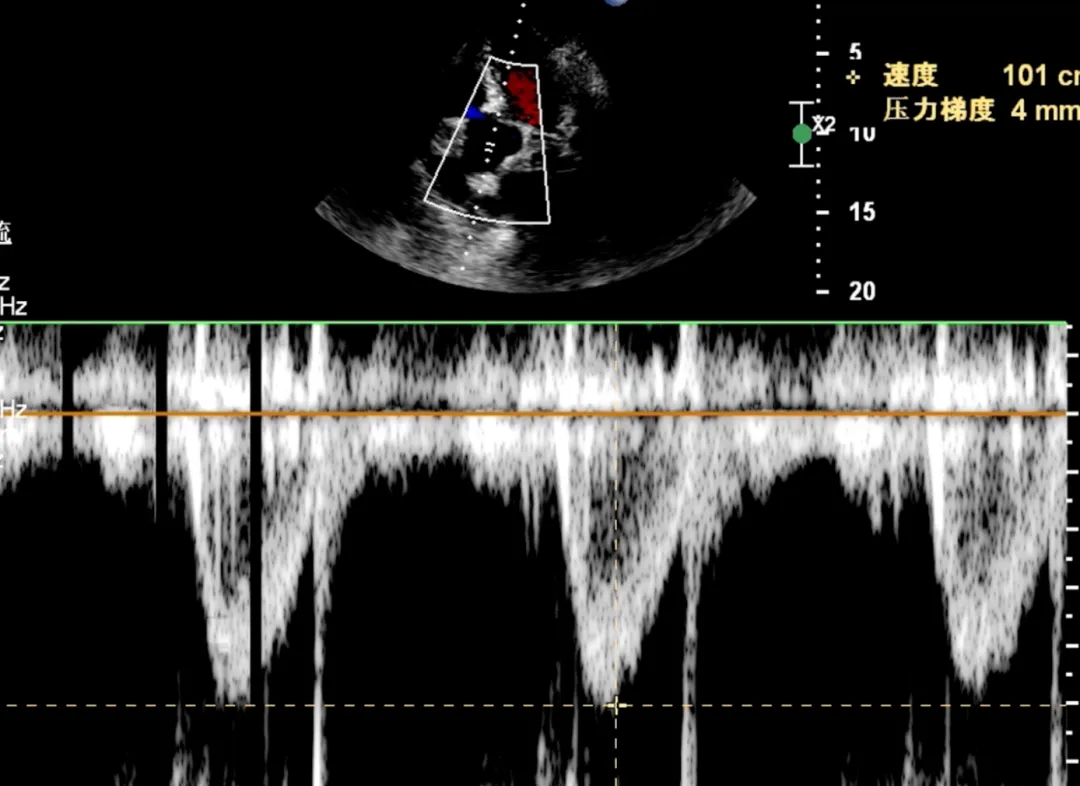

第二房间隔呈“搭错样”改变,通道宽约2.8mm,长约12mm。

术中复测:PFO宽约2.8mm,长约12mm;膨出瘤大小约26X12mm。